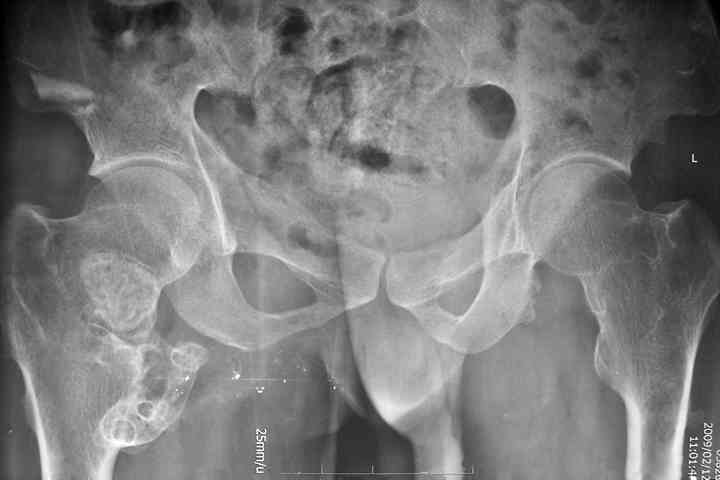

以下是引用余辉在2009-2-22 8:40:00的发言:[br]病变为双侧多发,双侧耻骨坐骨可能均有病灶

以下是引用zsl6918在2009-2-22 8:44:00的发言:[br]支持多发性骨软骨瘤